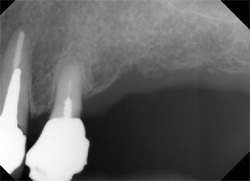

| CT撮影とともに局所のレントゲン撮影で5mm鋼球を写し込み上顎洞までの距離を把握し、インプラントのサイズを決定します。 |

|

| インプラントのフィックスチャーが埋入されました。 十分な組織の治癒と骨との接合(オステオインテグレーション)を確認した後、約3ヶ月経過後アバットメントを装着し、上部構造体を調製します。 |